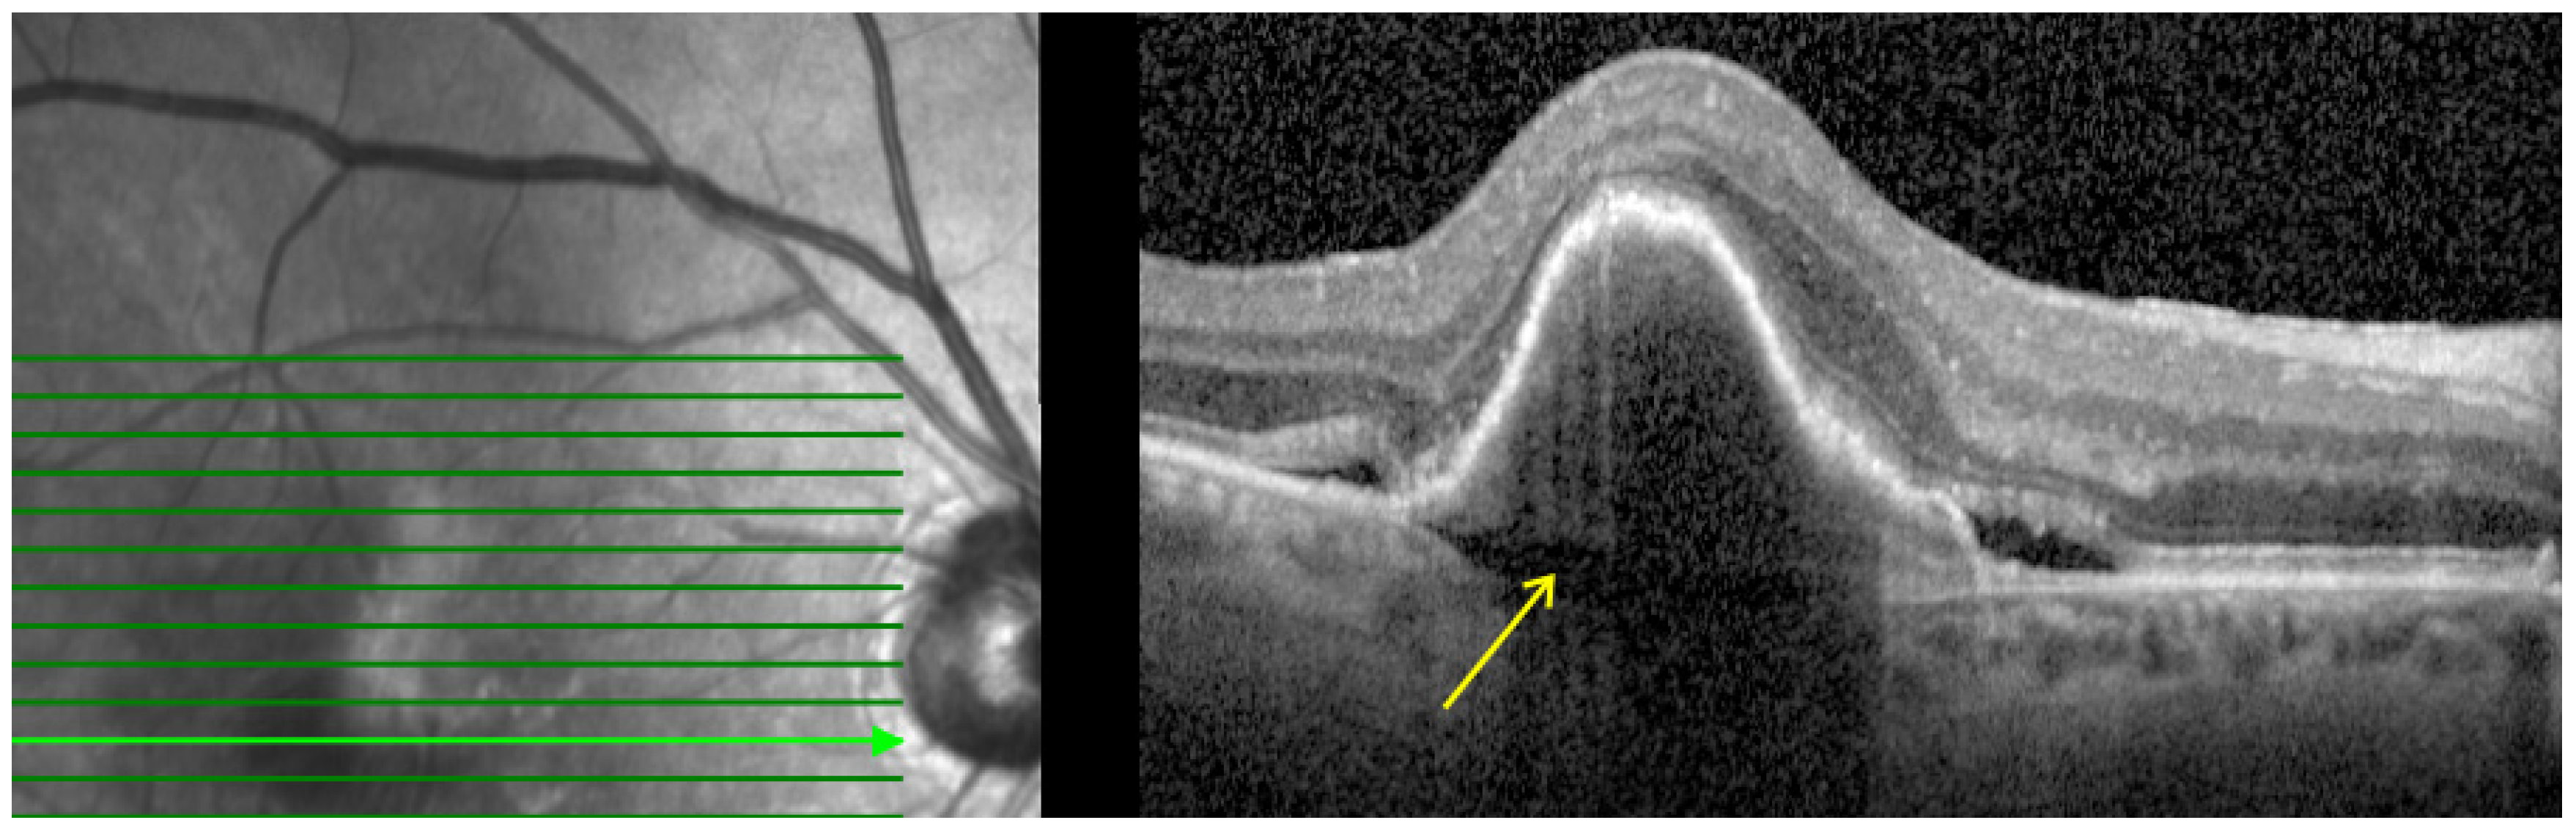

- Prechoroidal cleft (PCC): Defined as hyporeflective space between the RPE fibrovascular tissue and Bruch membrane as shown in Figure 4. PCCs are closely associated with a poor visual prognosis and increased risk of submacular hemorrhage or RPE tear [15]. The origin of the cleft has been attributed to a possible accumulation of the fluid generated by the fibrovascular tissue. However, its correlation with lesion activity and treatment remains unknown [32].